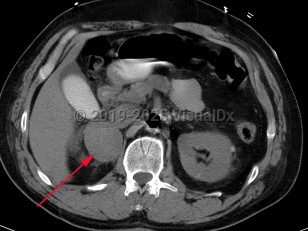

Pheochromocytoma

Pheochromocytoma (PCC) is a rare catecholamine-secreting neoplasm of adrenal origin; when it is extra-adrenal, it is referred to as paraganglioma. PCC is known as the "great masquerader" because of its similarity in clinical presentation to many other conditions. Up to 15% of patients may be asymptomatic. The most common presenting symptoms are hypertension (including labile hypertension), palpitations, increased sweating, severe headache, tremors, pallor, and dyspnea. Atypical symptoms include anxiety, abdominal pain, nausea, vomiting, constipation, insomnia, and weight loss. The prevalence of PCC in patients with hypertension is less than 0.2%. Rarely, paragangliomas may occur in the heart. Cardiovascular complications of catecholamine excess are rare but can lead to stress cardiomyopathy. Clinical presentation is characterized by transient duration of symptoms (eg, 15-20 minutes) that may recur several times a day. Physical exertion (moderate to extreme exercise) or bowel movements may provoke symptoms. Sometimes a pheochromocytoma is found incidentally during a workup.

Treatment involves surgical removal of the tumor after adequate medical therapy is provided, generally with combined alpha- and beta-adrenergic blockade. Tumors can recur in less than 10% of patients. Surgery may help return norepinephrine and epinephrine levels to normal. Despite perioperative management, acute hypertensive crises may develop during surgical resection. Management of acute hypertensive crisis due to pheochromocytoma includes nitroprusside, phentolamine, or nicardipine.